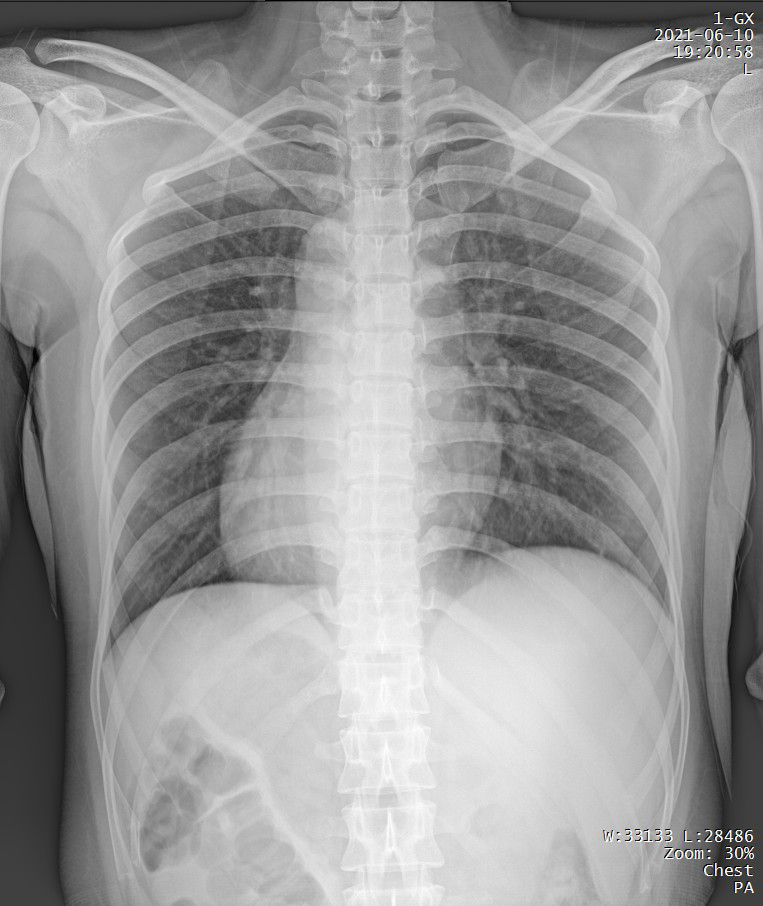

短時(shí)曝光 定格心肺運(yùn)動瞬間的影像

PLX5500能夠在短時(shí)曝光內(nèi)輸出足量的X射線,獲取清晰圖像。特別適用于拍攝肺炎、塵肺病、肺結(jié)核等難以憋氣的患者,避免因患者呼吸而產(chǎn)生運(yùn)動偽影,便于醫(yī)生準(zhǔn)確診斷。

支持高千伏攝影 肺部紋理更有層次

PLX5500能夠輸出高能量X射線,與骨骼相重疊的軟組織或骨骼本身的細(xì)小結(jié)構(gòu)及含氣的管腔等,均可清晰顯示。

Clinical picture

臨床圖片